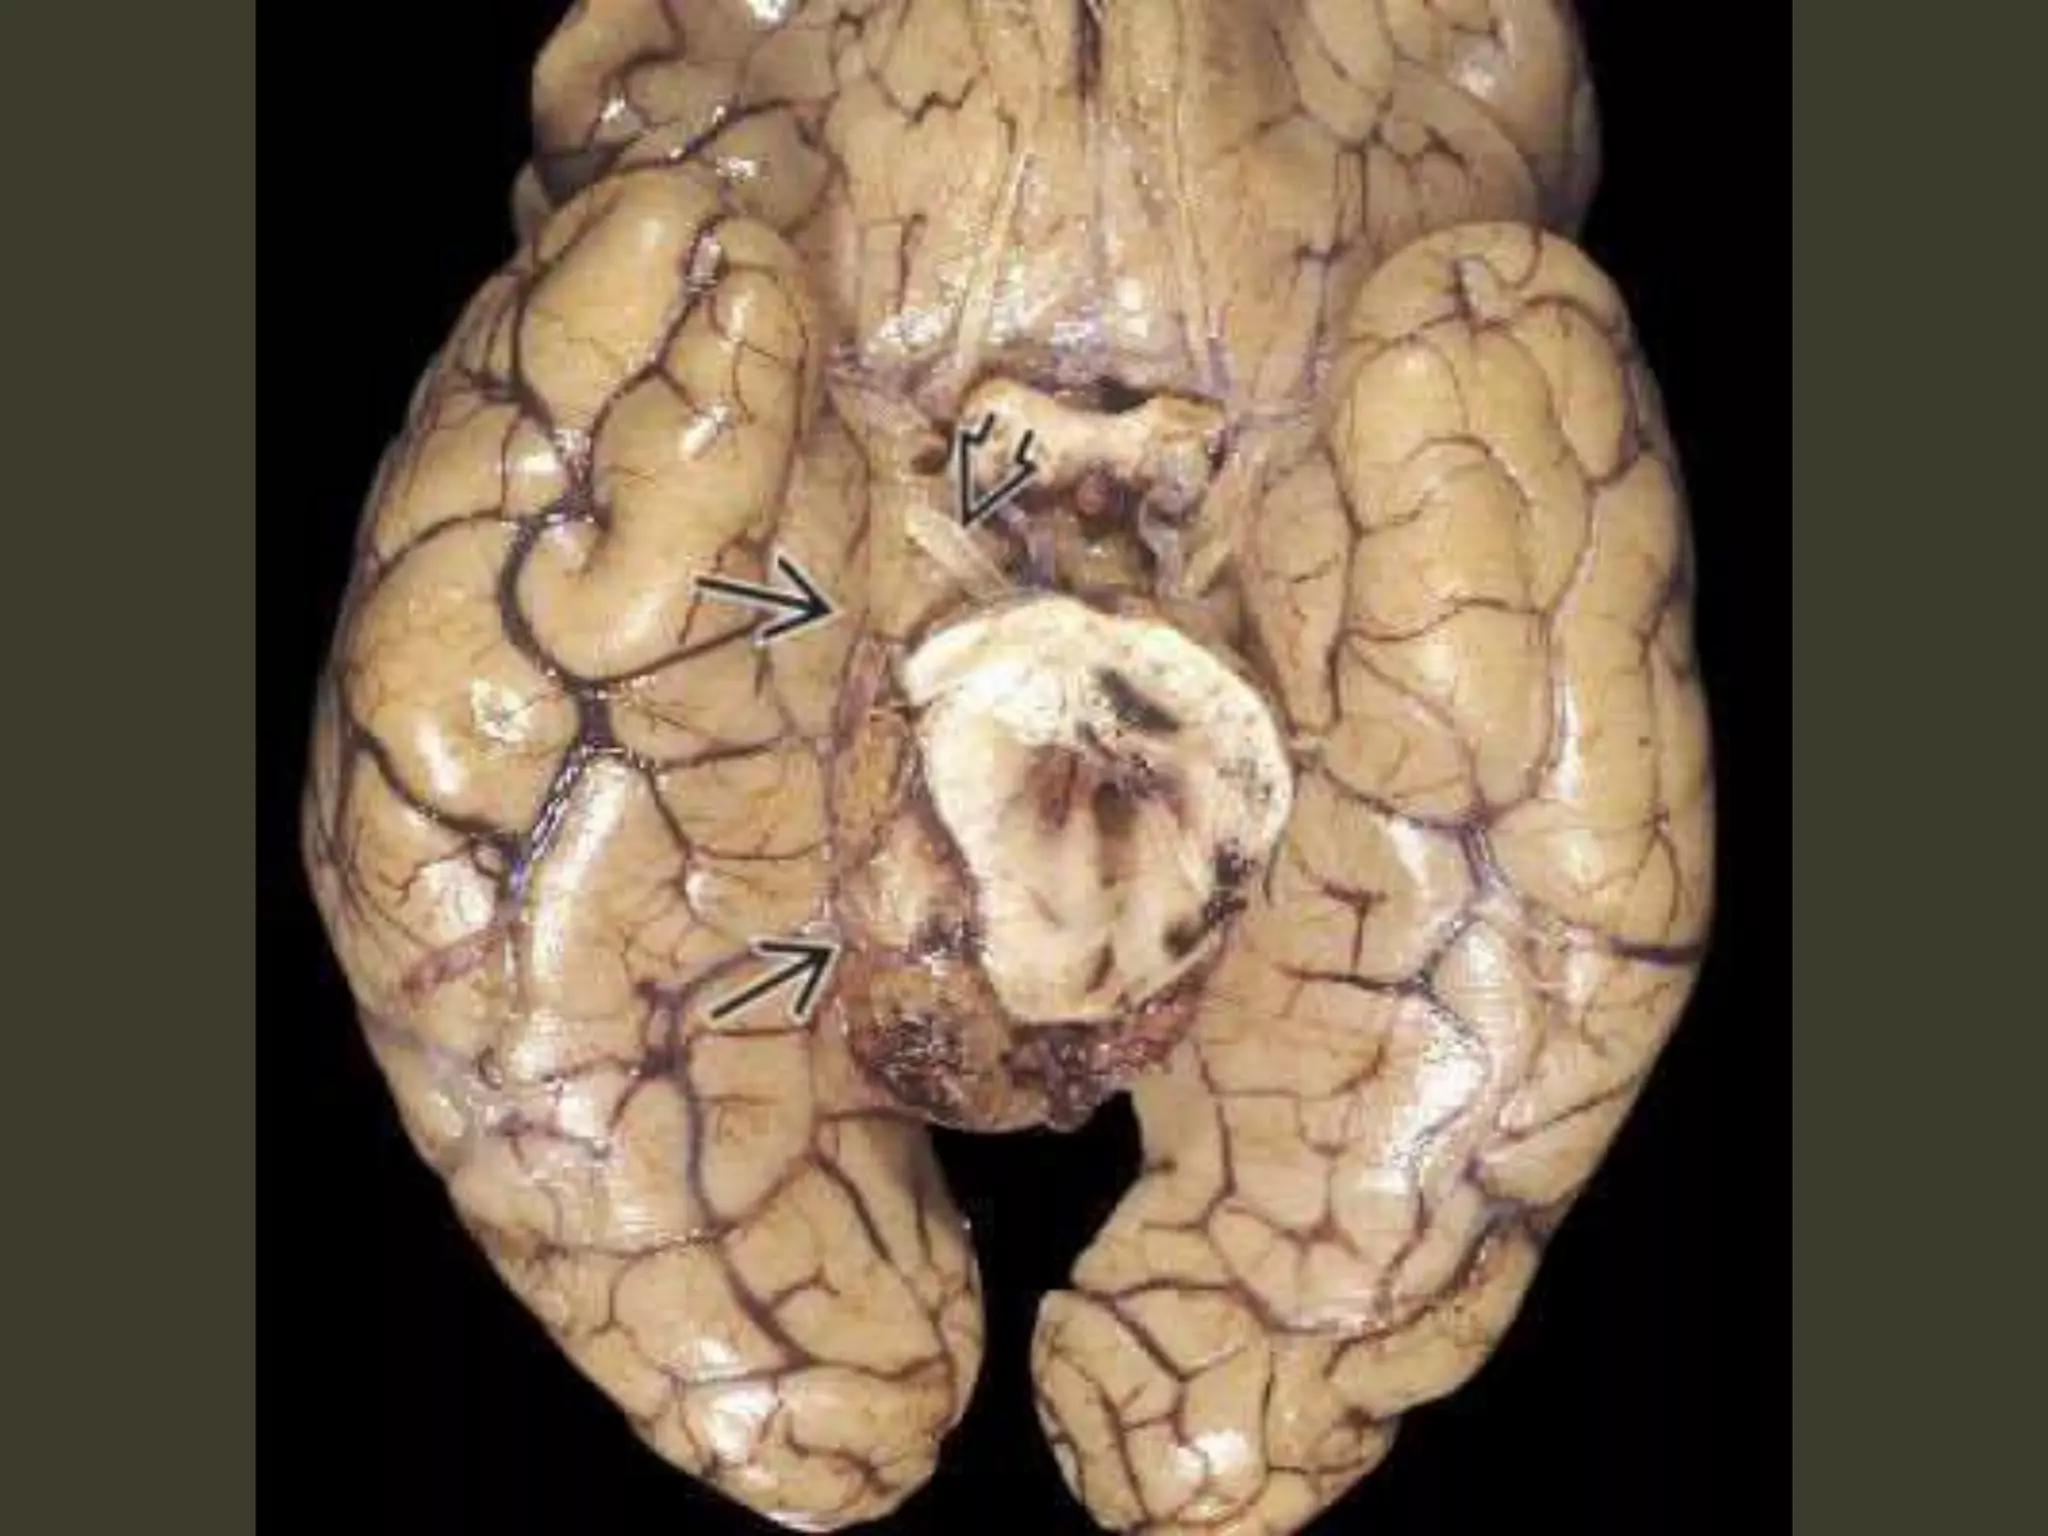

Subfalcine herniation

• supratentorial mass in one hemicranium

• affected hemisphere pushes across the midline

under the inferior "free" margin of the falx,

Subfalcine herniation: imaging

Axial and coronal images show that

•cingulate gyrus

•anterior cerebral artery (ACA)

•internal cerebral vein (ICV)

are pushed from one side to the other under the

falx cerebri.

The ipsilateral ventricle appears compressed

and displaced across the midline

Complications

• unilateral obstructive hydrocephalus

– foramen of Monro occlusion

• Periventricular hypodensity with "blurred"

margins of the lateral ventricle

– Fluid accumulates in the periventricular white

matter

• When severe, the herniating ACA can be

pinned against the inferior "free" margin of

the falx cerebri

🡪 secondary infarction of the cingulate gyrus